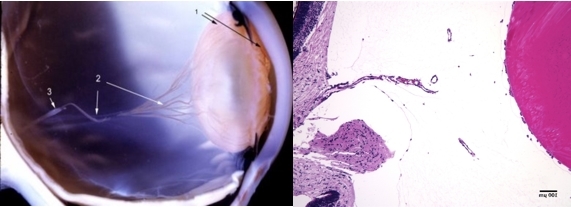

- The hyaloid artery (“3”, left) feeds the vasa hyaloidea propria (“2”, left) which anastomosis with the tunica vasculosa lentis (“1”, left). The histologic section to the right is stained with H & E (bar = 100 uM) [Left: from Yee at al.: Vitreous cytokines and regression of the fetal hyaloid vasculature. In: Vitreous – in Health & Disease. Springer, New York, 2014; pg. 42 (image © Springer Nature, reprinted with permission) Right: from Sebag J: Vitreous and vitreo-retinal interface. In: Ryan’s Retina 6th edition (A. Schachat, ed.) Elsevier, 2018; pg. 546.